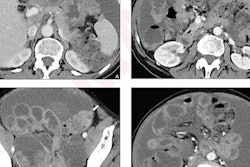

Although surgeons use a scoring system called a peritoneal cancer index (PCI) to divide the abdomen into 13 regions and measure the extent of disease, Lahaye's research showed that a special step in a surprise preoperative DW-MRI scan was especially useful.

"We have quite a simple MRI protocol: T2-weighted images, T1 pre- and postcontrast, and of course diffusion-weighted images," Lahaye said. "And I can't stress this enough: People have to drink one liter of pineapple juice because this will result in a nice quality because it will suppress the high signal on the diffusion-weighted images in the bowel. Because I don't want to see bowels, I want to see cancer. So please, use pineapple juice when you use these protocols."

Lahaye's team found that MRI could predict a complete primary and interval debulking and did so "quite accurately" in the primary group (AUC 0.9) and in the interval group (AUC 0.83). He cautioned, though, that for lesions below 4 mm MRI will still struggle to see them. Lahaye also noted good interobserver agreement (0.81).

"We as radiologists have a problem in depicting disease on CT, peritoneal disease. We have a sensitivity of 11% for lesions smaller than 5mm. That's really low. While on MRI, especially on diffusion-weighted images, these lesions light up like a lightbulb," he said.